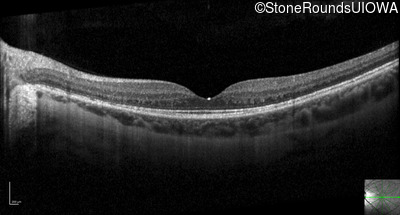

Optical Coherence Tomography - Right - 20/40 +1

Exemplar / OCT Stack